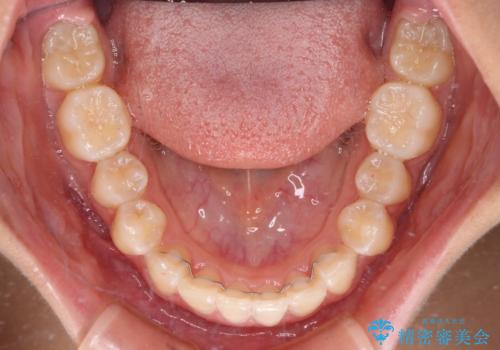

奥歯の咬み合わせと深い咬み合わせを改善した後、隙間などをインビザラインで整えることとしました。

インビザラインをしっかりと装着したことはもちろん、高校生は歯の動きが早いため、非常に短期間で治療を終えることができました。